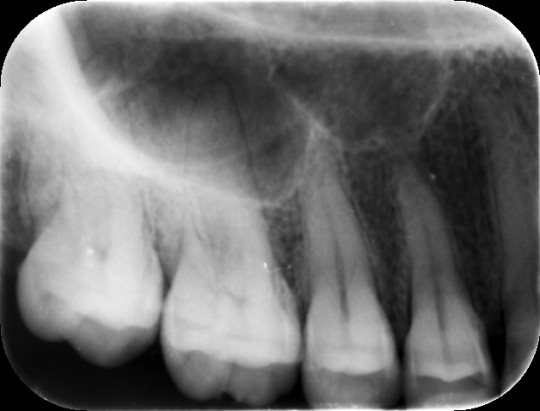

Apikální projekce patří mezi nejčastěji používané techniky. Na snímku můžeme vidět celou korunku zubu, krček, kořen s kořenovými kanálky, okolí kořene zubu, periodontální štěrbinu s kostí alveolárního výběžku. Zhotovení snímku probíhá ve spolupráci s pacientem, který si rentgenový snímek přidržuje sám v ústech, nebo za pomoci držáků určených pro tento typ projekce.

Na rtg snímcích zhotovených apikální projekcí můžeme detailně vidět zubní kazy, amalgámové či kompozitní výplně, resorpci alveolární kosti, kořenovou výplň po endodontickém ošetření, nález na hrotu kořene (periapikální projasnění), resorpci či frakturu kořene, či průběh periodontální štěrbiny.

Obr. 16. Apikální snímek